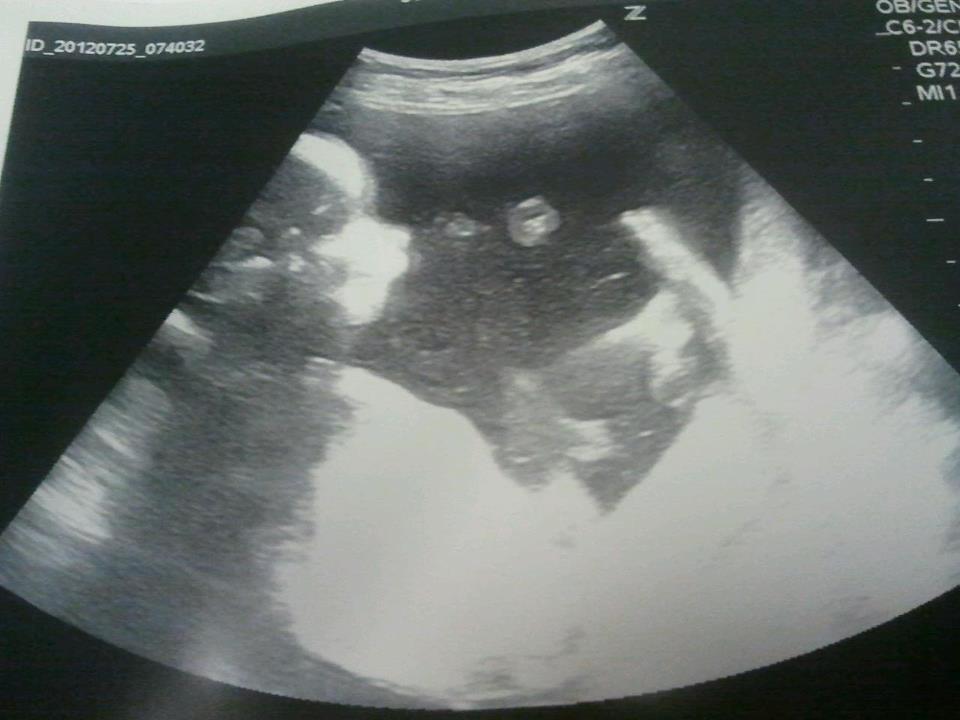

Lillah Skrevet 25. juli 2012 Forfatter #241 Skrevet 25. juli 2012 (endret) I dag har vi vært på sykehuset til ordinær ultralyd. Inni magen skjulte det seg en liten prins, som ikke var redd for å vise seg fram. Så selv hva det var med en gang. Aktiv liten krabat Ultralydbildene ble ikke så veldig bra.. Da han rørte på seg hele tiden, men når vi så han på skjermen var det helt magisk!! Ble forresten satt 2 dager tilbake, så ny termindato er den 19.desember. Endret 25. juli 2012 av Lillah